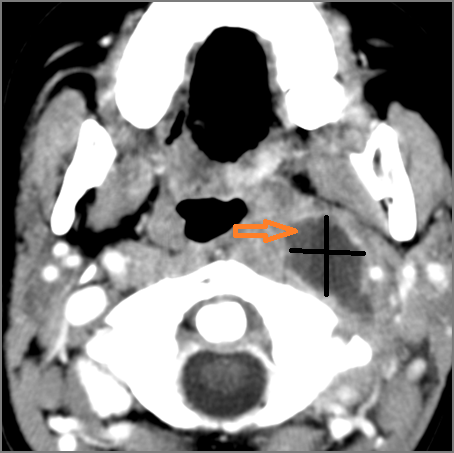

There is suppurative retropharyngeal lymphadenopathy. [Yes/No]

If there is suppurative retropharyngeal adenopathy what is the maximum short axis dimension of the largest suppurative node. MEASUREMENT [Yes/No]

There is related edema/abscess within the adjacent parapharyngeal/retropharyngeal spaces. [Yes/No]